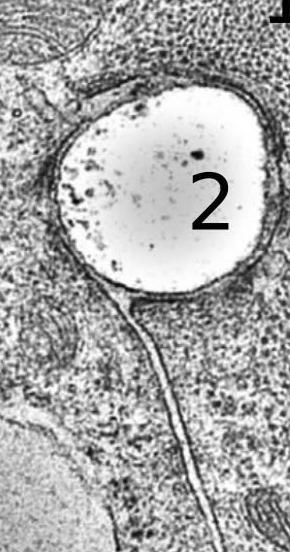

“使用三种独立的方法,我们发现在纳米纤维支架上开发时,心肌细胞在所有侧面包裹纤维,在大多数情况下形成'鞘'结构。可激发生物物理实验室负责人Konstantin Agladze教授解释道。系统。“相比之下,成纤维细胞具有更坚固的结构和与基质相互作用的更小区域,仅在一侧接触它。”

生长,发育和再生组织形成的重要性是细胞生长的底物。用于心脏组织工程的支架基于聚合物纳米纤维基质。纳米纤维在弹性和导电性方面可以变化,或者它们可以具有额外的“智能”功能,允许它们在特定阶段释放生物活性分子。

纳米纤维被设计成模仿细胞外基质,其围绕细胞,提供结构支持。此外,纳米纤维可用作将物质输送到周围细胞中以诱导其中的生物化学变化的介质。因此,研究支架和心脏细胞之间的相互作用对于选择正确的纳米纤维特征至关重要 。